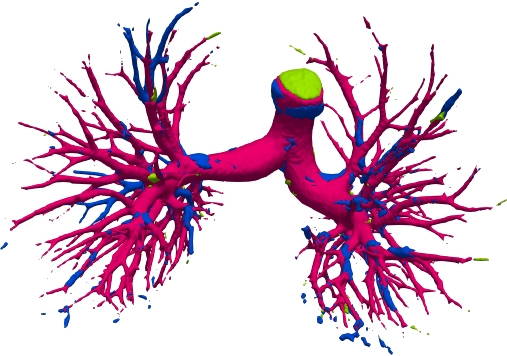

We qualitatively analyze our method on four challenging lung organ datasets. In Fig. 5, SFCN [19] suffers from severe false positives and some false negatives, especially for the big green areas of airway leakages. WNet [22] is mainly influenced by false negatives on the main trachea. For the Fibrosis dataset at the third row, it also encounters the false negative problem in the terminal bronchioles moderately. FANN [10] bears the slight discontinuity issue of false negative in the terminal bronchioles of BAS dataset, and the severe discontinuity and airway leakage problems on the more challenging Fibrosis benchmark. Instead, due to the above two novel modules, our method can solve the defects of false negative, discontinuity, and leakages faced by past advanced methods. Besides, the results on PARSE22 artery dataset in supplementary Fig. 6 also proves this.